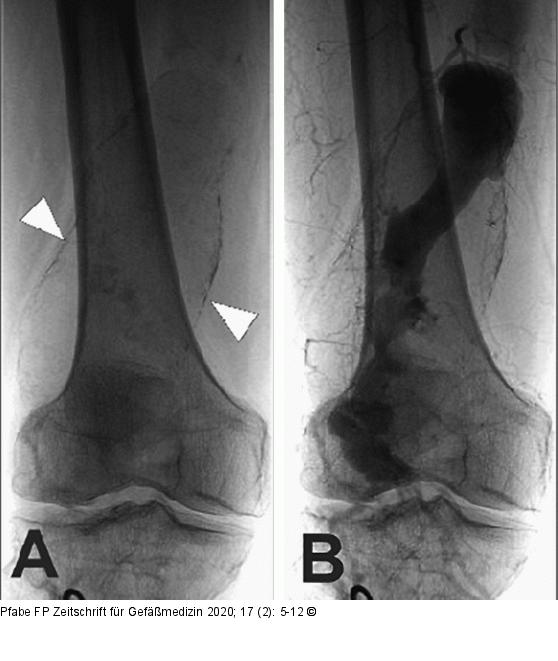

Abbildung 6A-B: PAA bei Arteriomegalie Angiographische Darstellung eines PAA bei Arteriomegalie. (A): Nativaufnahme mit Konturierung des Aneurysmasacks (Querdurchmesser 63 mm) bei kalzifizierter, degenerativ veränderter Arterienwand (weiße Pfeile); (B): Diskrepanz zwischen durchströmtem Lumen und wahrer Größe des Aneurysmas als Hinweis für eine partielle Thrombosierung des Aneurysmasacks. |

Abbildung 6A-B: PAA bei Arteriomegalie

Angiographische Darstellung eines PAA bei Arteriomegalie. (A): Nativaufnahme mit Konturierung des Aneurysmasacks (Querdurchmesser 63 mm) bei kalzifizierter, degenerativ veränderter Arterienwand (weiße Pfeile); (B): Diskrepanz zwischen durchströmtem Lumen und wahrer Größe des Aneurysmas als Hinweis für eine partielle Thrombosierung des Aneurysmasacks. |